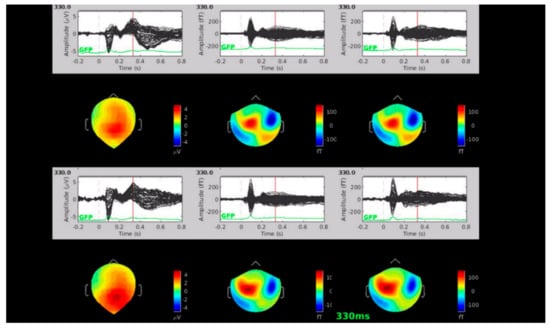

3. Results